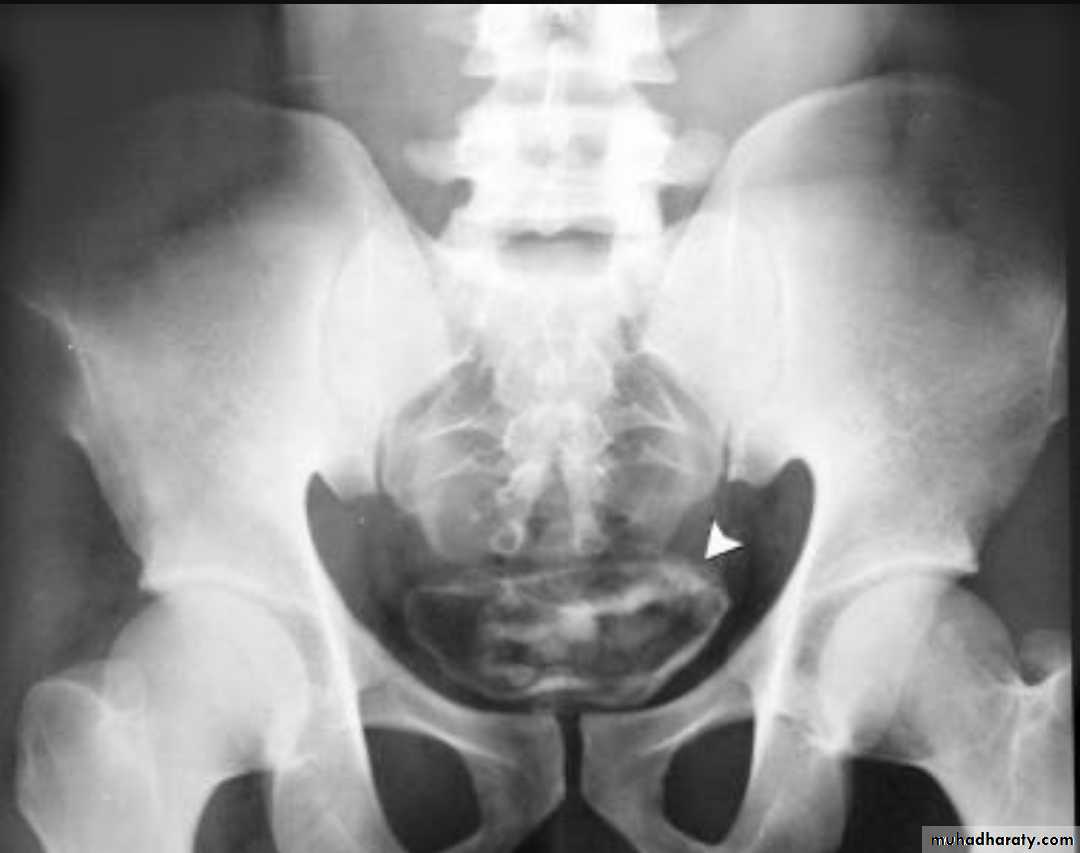

Renal stones

High density renal stonesStage horn calculus KUB filmsradio opaque stones